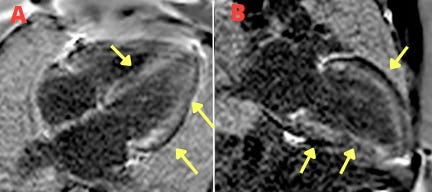

Imagem da Semana

Paciente em investigação de cardiopatia infiltrativa. Realiza ressonância magnética cardíaca que identifica um clássico padrão de realce tardio subendocárdico e difuso (setas). O diagnóstico: amiloidose cardíaca.